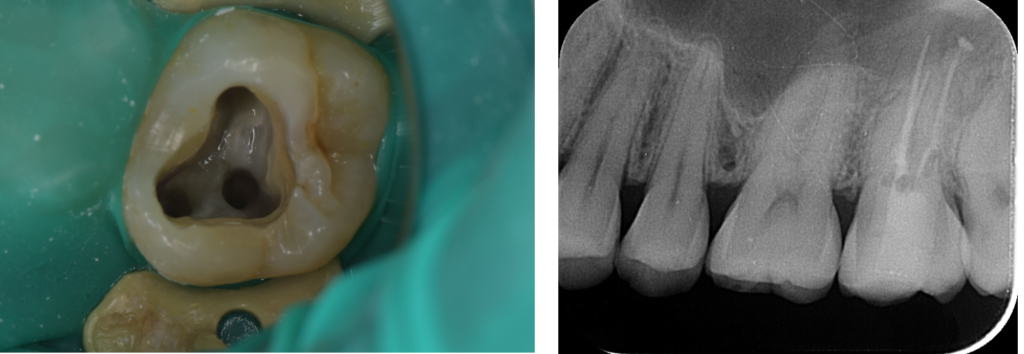

精密根管治療とは?歯を残すために本当に大切な選択

「できるだけ歯を抜きたくない」「何度も同じ歯が痛くなる」「根の治療をしたのに治らない」

このようなお悩みをお持ちの方にこそ知っていただきたいのが、精密根管治療です。

根管治療とは、虫歯が神経まで達した場合や、過去に治療…